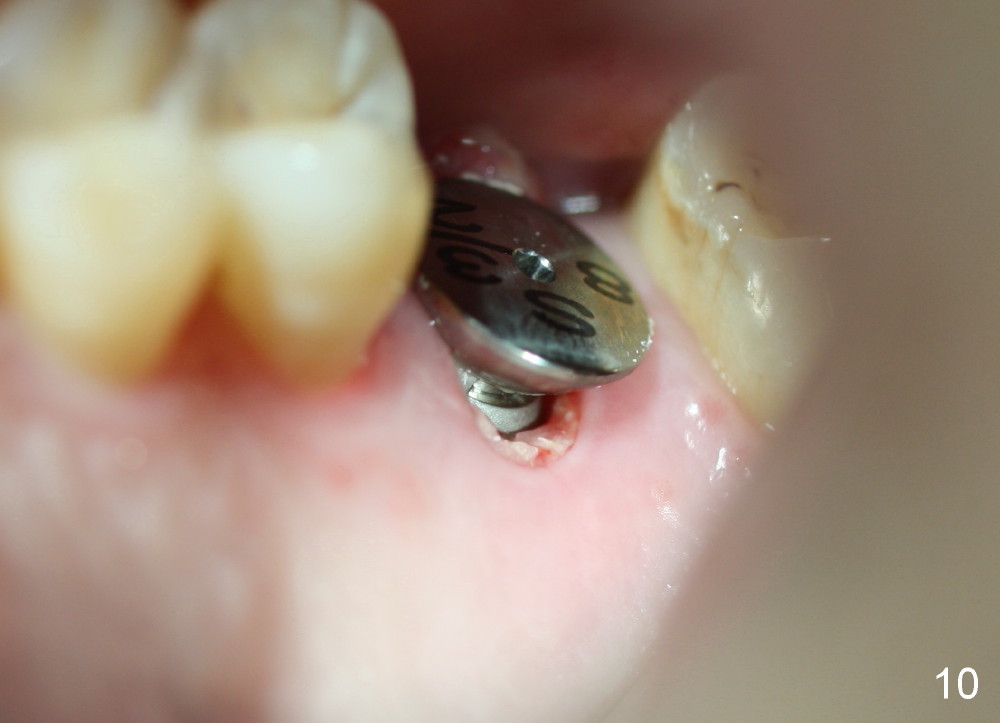

A 45-year-old man has lost the tooth #14 for a while (Fig.1); bone height is 5.4 mm. An extra wide and short implant is planned. Torus palatinus is large, suggesting that bone density should be high. A 6 mm tissue punch is chosen, but it is placed more palatal. If it were placed in the middle of the ridge, there would be no buccal keratinized gingiva (incision may avoid this issue). Additionally, the buccal portion of punch is made incomplete so that there is pedicle on the buccal side when the flap is raised (Fig.4,8: F). It is expected that the excess portion of keratinized tissue will form thick gingiva buccally. Osteotomy proves that bone is dense (Fig.2 (4.5x11 mm tap). Typical sinus lift is finished with placement of 6.4x6 mm (extra wide) bone-level implant (Fig.3, >55 Ncm). Following further torque, Fig.4 shows that the implant (I) is sub-gingival (<). Bitewings are taken to confirm that the implant plateau is at the crestal level (Fig.5,6 ^). PA shows sinus lift (Fig.7 *). The lingual aspect of the implant and healing abutment (H) is further bone grafted and covered by collagen dressing (Fig.8 *). The wound is protected with perio dressing. When the latter dislodges 7 days postop, the collagen dressing and bone graft are lost as well (Fig.10), while the buccal flap remains vital (Fig.9). The lingual exposed plateau should be able to heal normal. The collagen dressing should have been fixed in place by suture or as simple as a dental floss. There is mild nasal hemorrhage 1-2 days postop, possibly related to sinus membrane perforation and inability of Collagen Dressing to cover the perforation and contain the bone graft. When the patient returns for #9 implant placement in 3 weeks postop, the buccal flap reduces in size (Fig.11 *), while the palatal wound has healed with minimal exposure of the implant (Fig.12). Sinus graft remains in place 3 months postop (Fig.13); the buccal flap appears to have incorporated into a part of the gingiva (Fig.14). The bone density of the sinus lift appears to increase 10 days later when an abutment is placed (Fig.15 *). Although oral hygiene is pristine, there is apparent crestal bone resorption 12 months (Fig.16) and 20 months (Fig.17) post cementation, probably due to unfavorable crown/implant ratio and bruxism as well as pre-implantation bone loss (Fig.18,19). In contrast, an immediate implant in the same patient avoids pre- or post-implantation bone loss. In fact both the soft (Fig.20) and hard (Fig.21) tissues remain healthy 2 years 8 months post cementation. The sinus lift remains 3 years 8 months post cementation (Fig.22), while the crestal bone loss persists. The patients keeps complains of food impaction distal associated with bad smell 4 years 1 month post cementation. In fact the distal proximal contact is within normal limit. The bad smell is probably due to crestal bone loss (Fig.23 (pan), 24 (CT) *) and periimplantitis. Bone graft, PRF and Cytoplast membrane will be needed and fixed in place with long healing screw. When the patient returns for crown redo, he also reveals floss related gingival hemorrhage. There is pain associated with palatal sulcus probing with light gingiva erythema. Review of CT coronal section shows possible palatal (Fig.25 P) bone loss (*).